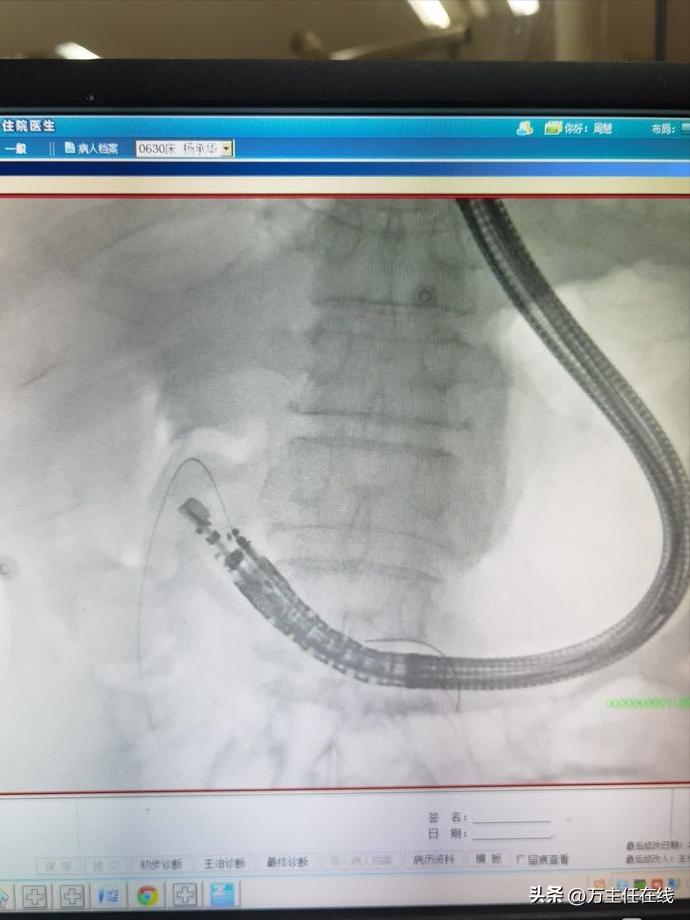

X线示腹腔内留置导丝位于积聚黏液内